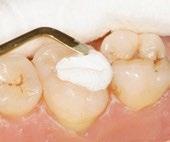

With the universal composite BRILLIANT EverGlow

highly aesthetic and long-lasting restorations can be achieved effortlessly.

Exceptional polishability and long-lasting brilliance

Aesthetic single-shade restorations

Versatile shade system with three translucency levels

Excellent sculptability and smooth consistency

Good wettability with minimal stickiness to the instrument

Initial situation: discoloration Opaque shade applied

HIGHLY AESTHETIC RESULTS Final restoration